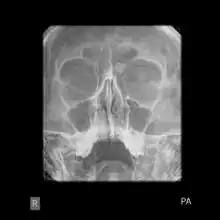

Medical imaging such as X-ray, CT scan and MRI show dense, clearly defined, round white tumors attached to bone.[1] They may be diagnosed when having medical imaging for another reason.[3] Osteomas of the paranasal sinuses and skull base can be diagnosed using CT-scan without intravenous contrast, allowing its size and relation to nearby important structures to be assessed.[3] A biopsy is not usually required.[3]

X-ray skull: Osteoma of the frontal sinus